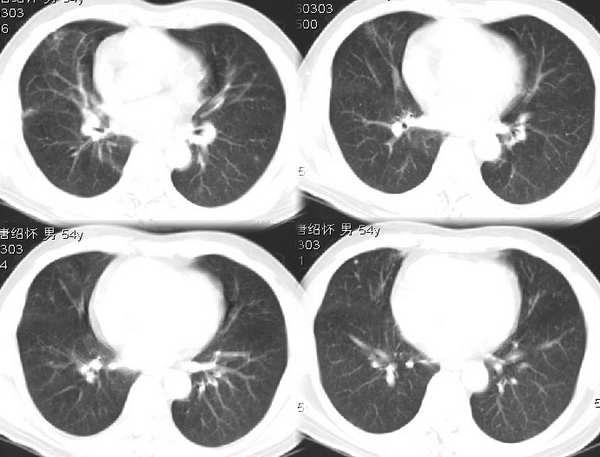

男54岁咳嗽咯痰2w,外院胸片示“右上大叶性肺炎抗炎治疗后部分吸收

右肺上叶少量间质炎性表现,结合病史为大叶性肺炎未吸收完表现。

该病人54岁,胸膜下可见多个类圆形透亮影,是不是还要考虑慢性/弥漫性肺疾病可能?

请问右中叶支气管开口旁不强化结节影是什么?

右上叶支气管变窄.ca?

右肺上叶少量间质炎性表现,大叶性肺炎吸收期。

考虑还是弥漫性间质性改变伴右肺炎症